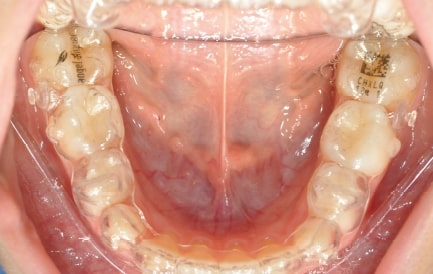

Malocclusion A6 Correction of Mandibular Retrusion in Growth phase patient | Skeletal Class II | Class II Division 1 malocclusion | Deep bite | Mixed dentition

Initial Photos and datas

Clinical examination and diagnosis

DENTAL:

• Molar and Canine class 2 on the right side – Molar and Canine clss 1 on the left side

• Upper diastema (11-21)

• Increased Overjet

• DeepBite

• Reduced Transversal Diameters

• Deviated Lower Midline 2 mm to the Right